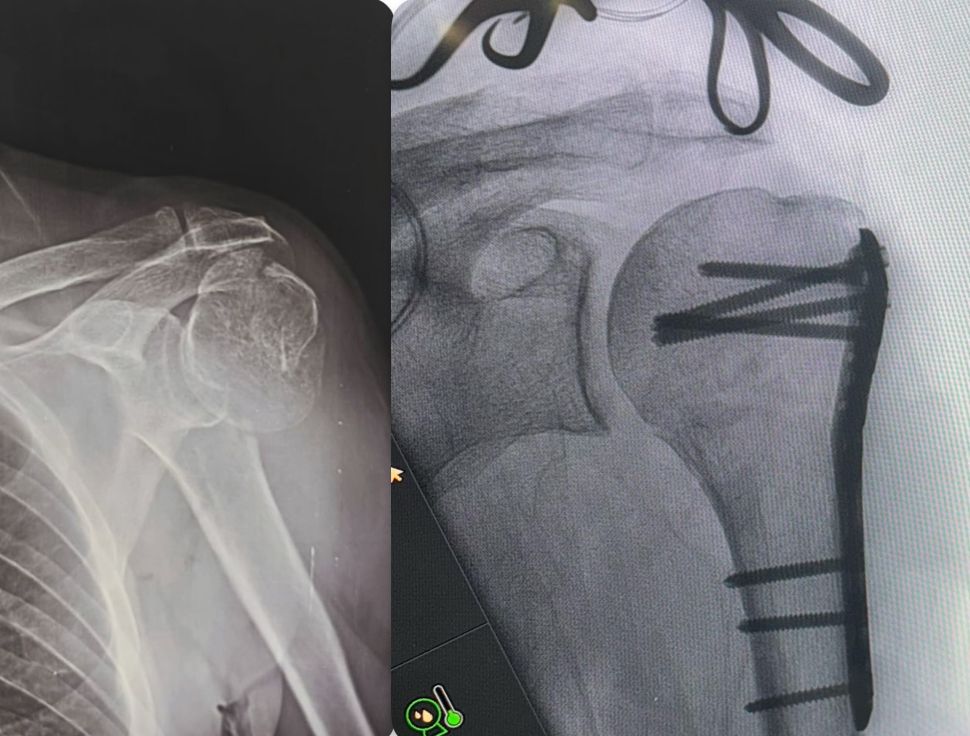

Fotos y videos